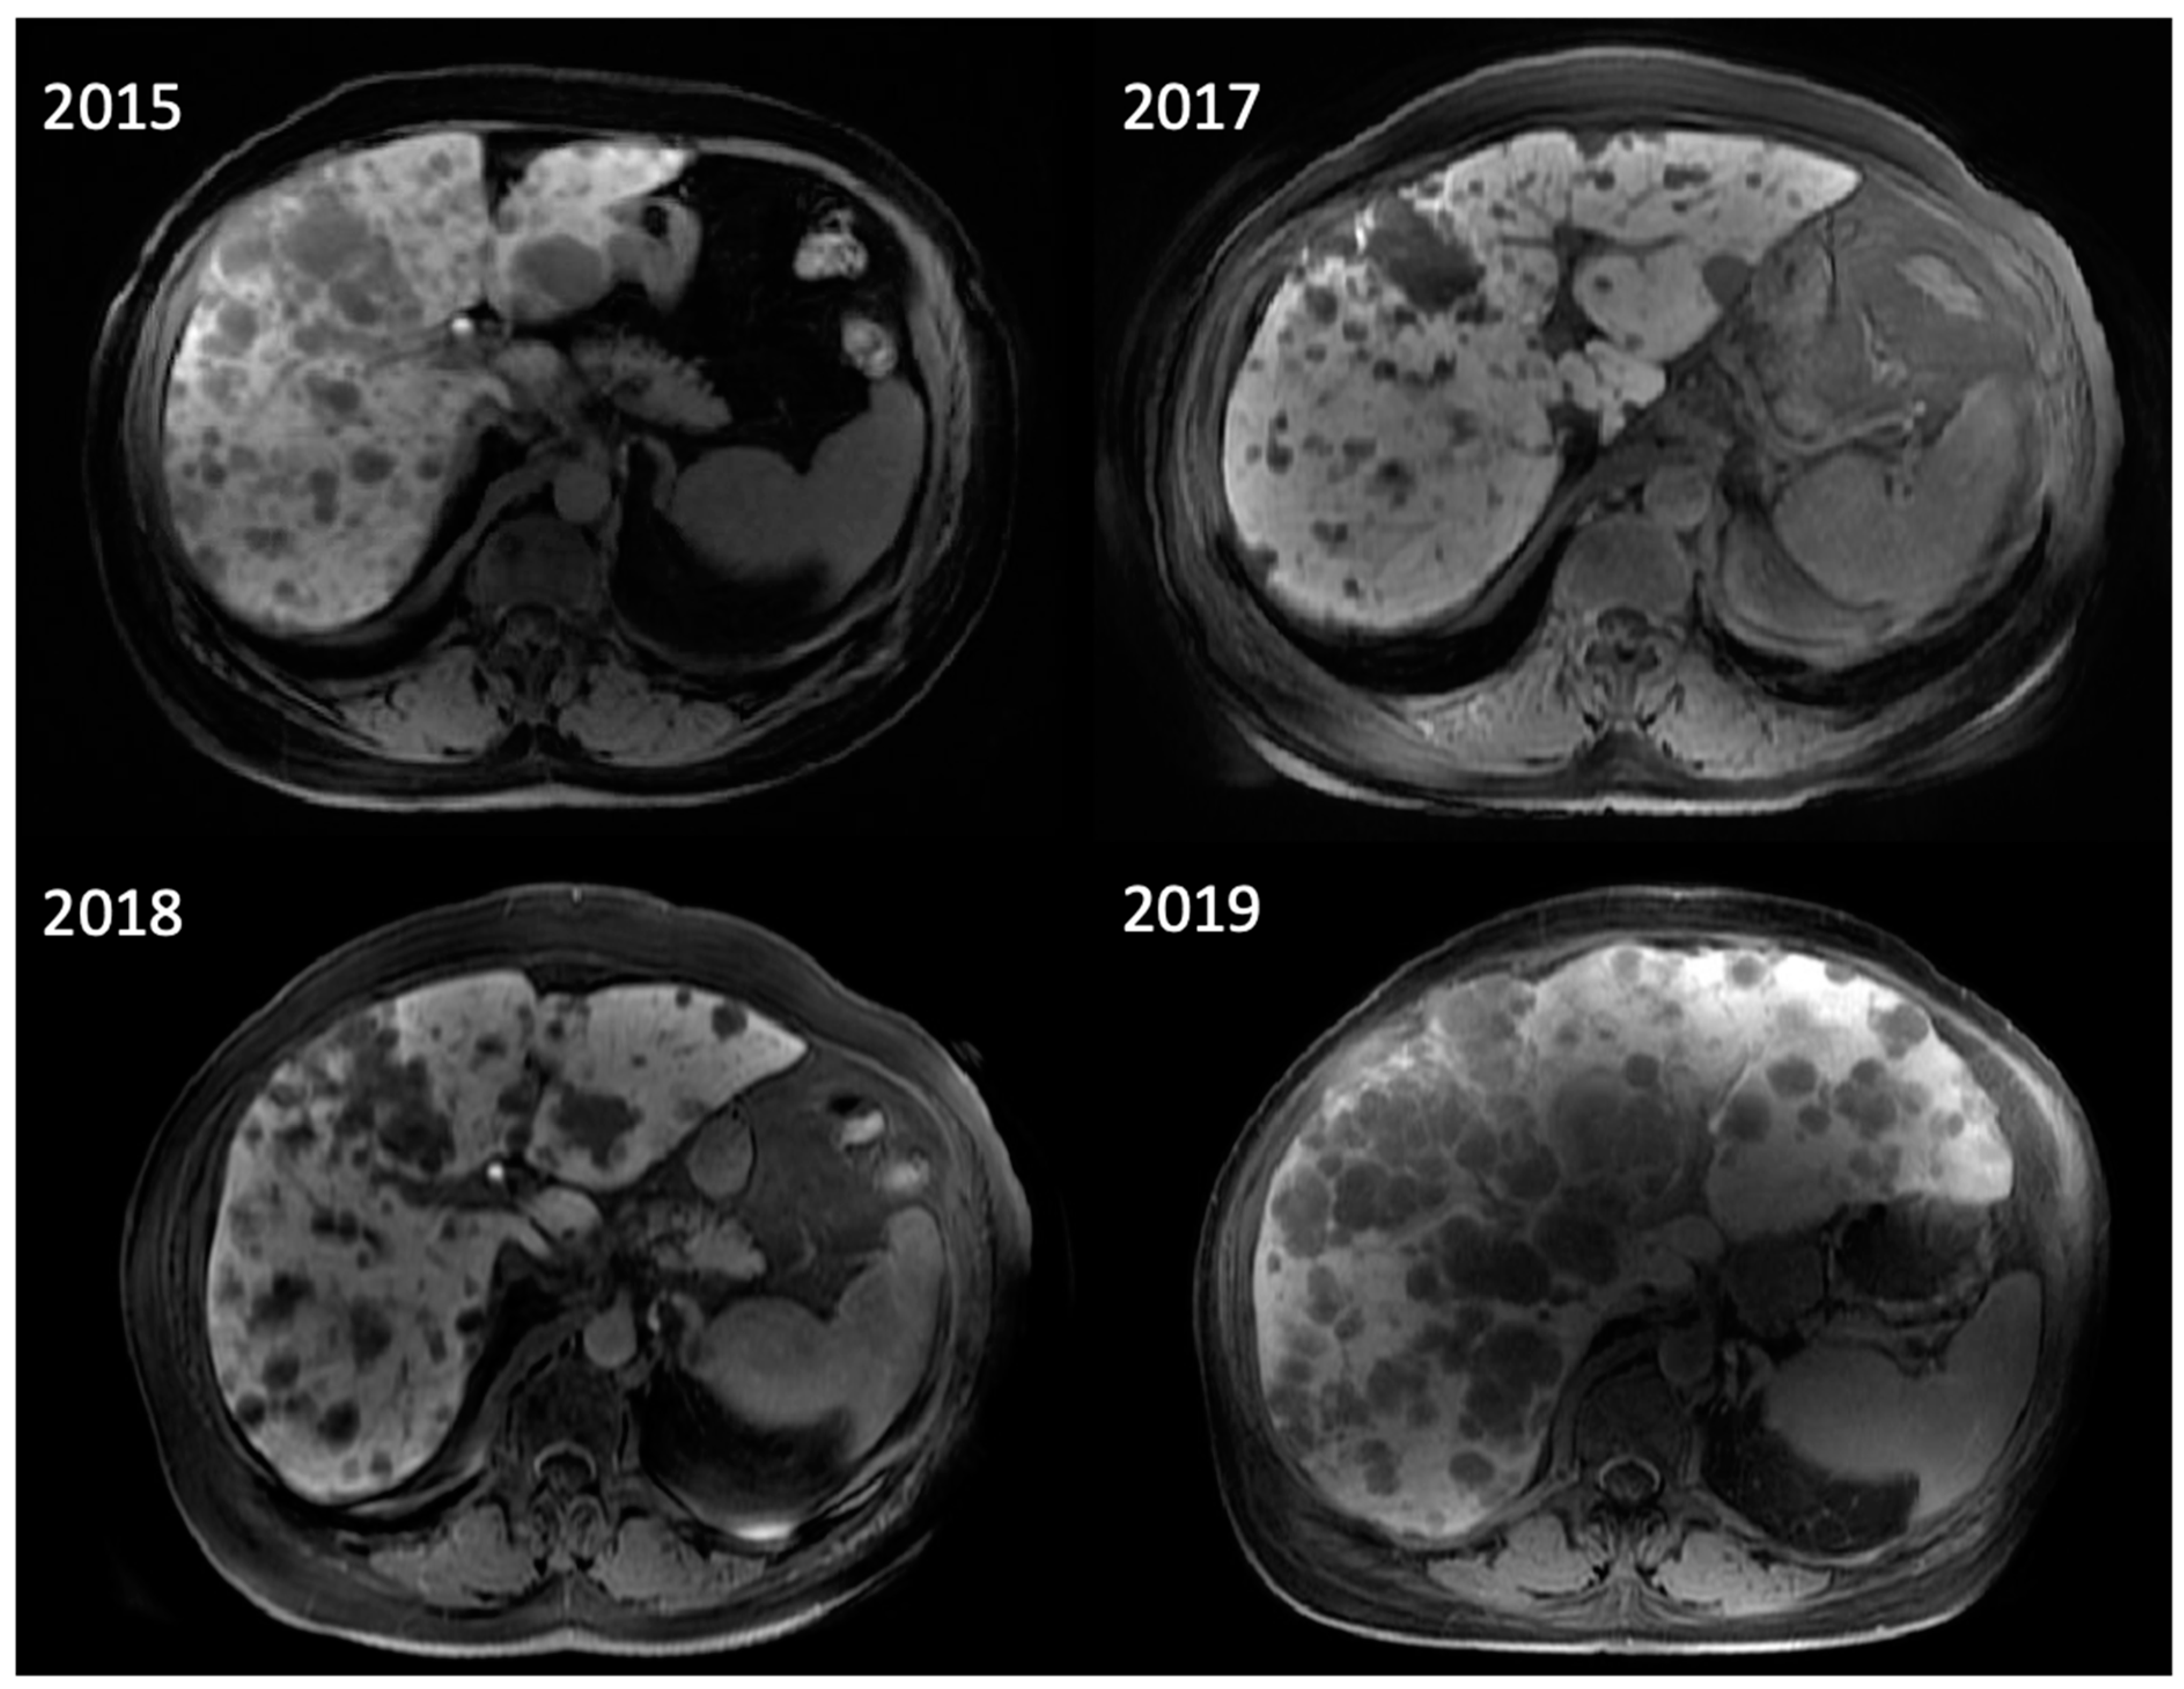

The subtypes have several differences that influence their management. CM metastasizes via the lymph system, most commonly to the lungs, liver, and brain. UM spreads via the circulatory system, owing to the extensive vasculature of the eye, most commonly to the liver [36] (Figure 2). Unlike CM, which is commonly detected via dermatological exam, primary UM sometimes presents with ocular symptoms when it invades the eye tissues, including blurred vision and seeing shadows [36].

Figure 2.

A 69-year-old woman with uveal melanoma metastatic to the liver post-treatment with tebentafusp, a bispecific antibody (BsAb), who developed cytokine release syndrome without radiologic imaging manifestations. Her large-burden liver disease was largely stable over the course of almost 3 years.